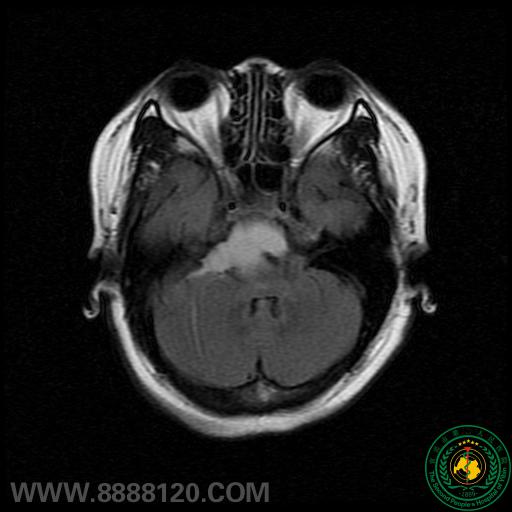

我科成功手术治疗脑干斜坡区占位病变一例

我科成功手术治疗脑干斜坡区占位病变一例6197